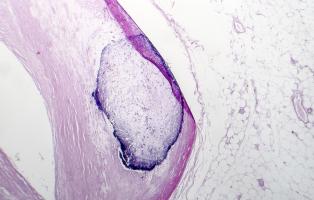

ATHÉROSCLÉROSE : Des nanoplastiques à côté de la plaque

Actualité publiée le 21/11/2024ATHÉROSCLÉROSE : Des caractéristiques cliniques cancéreuses ?

ATHÉROSCLÉROSE : Réaliser les promesses des sphingolipides

ATHÉROSCLÉROSE : La plaque plus tardive mais plus nocive chez les femmes ménopausées

ATHÉROSCLÉROSE : Mais comment stabiliser la plaque ?